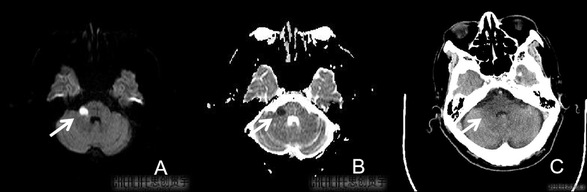

脑梗死发病后6 h内,颅脑CT检查常显示脑组织密度无明显变化,脑梗死发病24 h后CT检查才发现边界清楚的低密度影,此时已经发展为不可逆的脑梗死,经常会错过最佳治疗机会。然而,DWI在脑组织缺血30min后即可发现水分子扩散受限,在DWI序列上开始呈现高信号,表观弥散系数(ADC)值开始降低。简而言之,DWI检查能发现早期CT所不能发现的病灶,如下图所示,本院患者发病后6h内DWI与CT检查结果。

本院患者,男65岁,发病后6h内的影像学检查:图A:箭头所指右侧桥臂超急性期脑梗死,DWI图呈高信号;图B:箭头所指右侧桥臂ADC图呈低信号,图C:箭头所指右侧桥臂CT图呈等密度。